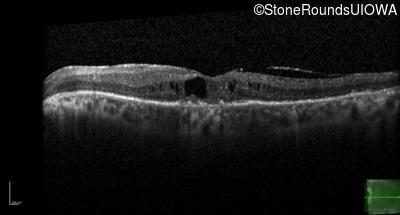

AR Retinitis Pigmentosa (IA1aiii)

Age at visit: 66 years

AR Retinitis Pigmentosa IFT172 Ala644Glu GCG>GAG Arg1284Stop CGA>TGA AR